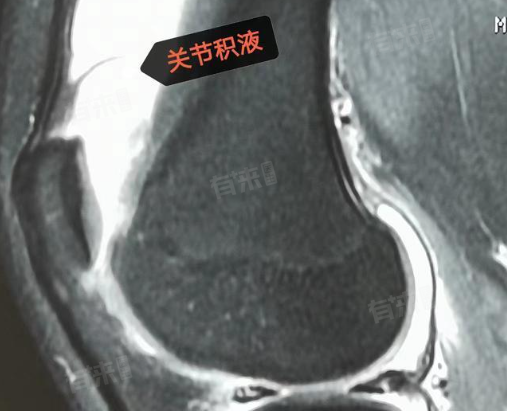

髌上囊积液并不完全等同于滑膜炎,但两者之间存在密切联系,滑膜炎是指滑膜受到刺激产生炎症,此时滑膜会出现充血、水肿,导致滑膜液的分泌增多与吸收减少,此类异常滑膜状态可以引起髌上囊积液的形成。

1、单纯髌上囊积液:创伤方面,如膝关节的直接撞击等外伤可能损伤关节周围组织,导致髌上囊出现积液,但滑膜本身并未发生炎症反应,关节退变方面,随着年龄增长,关节软骨磨损等关节退变过程中,关节腔内的压力变化等因素可能导致髌上囊积液,此时也不一定存在滑膜炎。

2、滑膜炎导致髌上囊积液:炎症介质会刺激滑膜细胞,使滑膜的通透性增加,原本正常的滑膜液分泌与吸收平衡被打破,过多的液体渗出并积聚在髌上囊等部位,滑膜炎的严重程度与髌上囊积液量有一定相关性。急性滑膜炎发作时,积液可能迅速增多;慢性滑膜炎可能导致积液反复出现,长期积累。